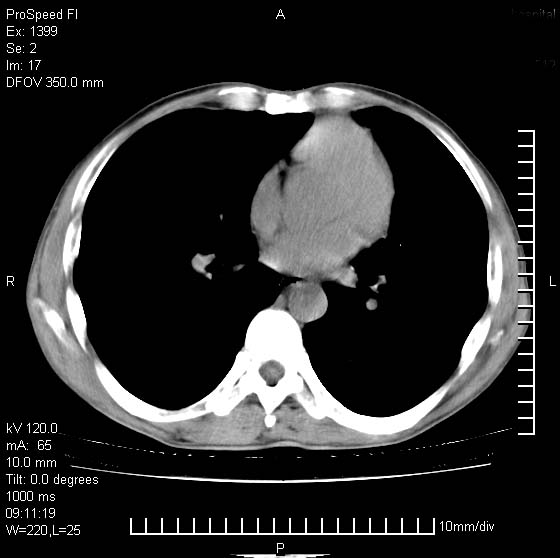

以下是引用卜一在2007-1-19 9:55:00的发言:[br]左肺沿胸膜下巨大肿块影,边缘呈分叶征,纵隔内见肿大淋巴结,右肺内另见一不规则结节影 .考虑:左肺周围性肺癌伴纵隔 右肺内转移.

以下是引用rgsyyf在2007-1-19 11:05:00的发言:[br]左肺上叶见形态不规则巨大软组织肿块影,边缘呈分叶征,纵隔内隆突下见肿大淋巴结,右肺内另见一不规则结节影 .考虑:左肺周围性肺癌伴纵隔即右肺内转移.